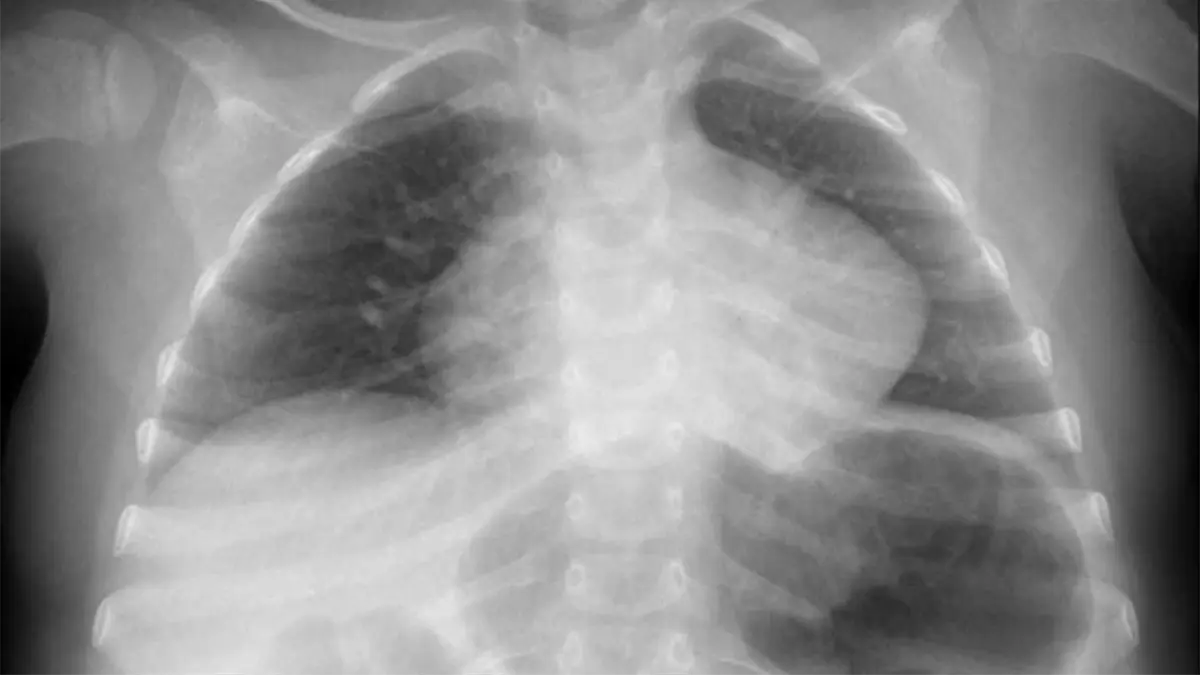

El pequeño Dylan, de apenas 2 años de edad, está delicado, ya que sufrió quemaduras graves en su esófago e infección en un pulmón, debido a que se tragó una pila, esto ocurrió en Hermosillo, Sonora.

La pila reventó en el interior de su organismo y provocó quemaduras en su estómago e infección en un pulmón.

La madre de Dylan, explicó que en un principio que lo llevó al Hospital de Cananea porque el niño presentaba dificultad para respirar y ahí le notificaron que había ingerido una pila.

Posteriormente, fue trasladado al HIES donde a través de diferentes aparatos oxigenan su sangre para poder operarlo.